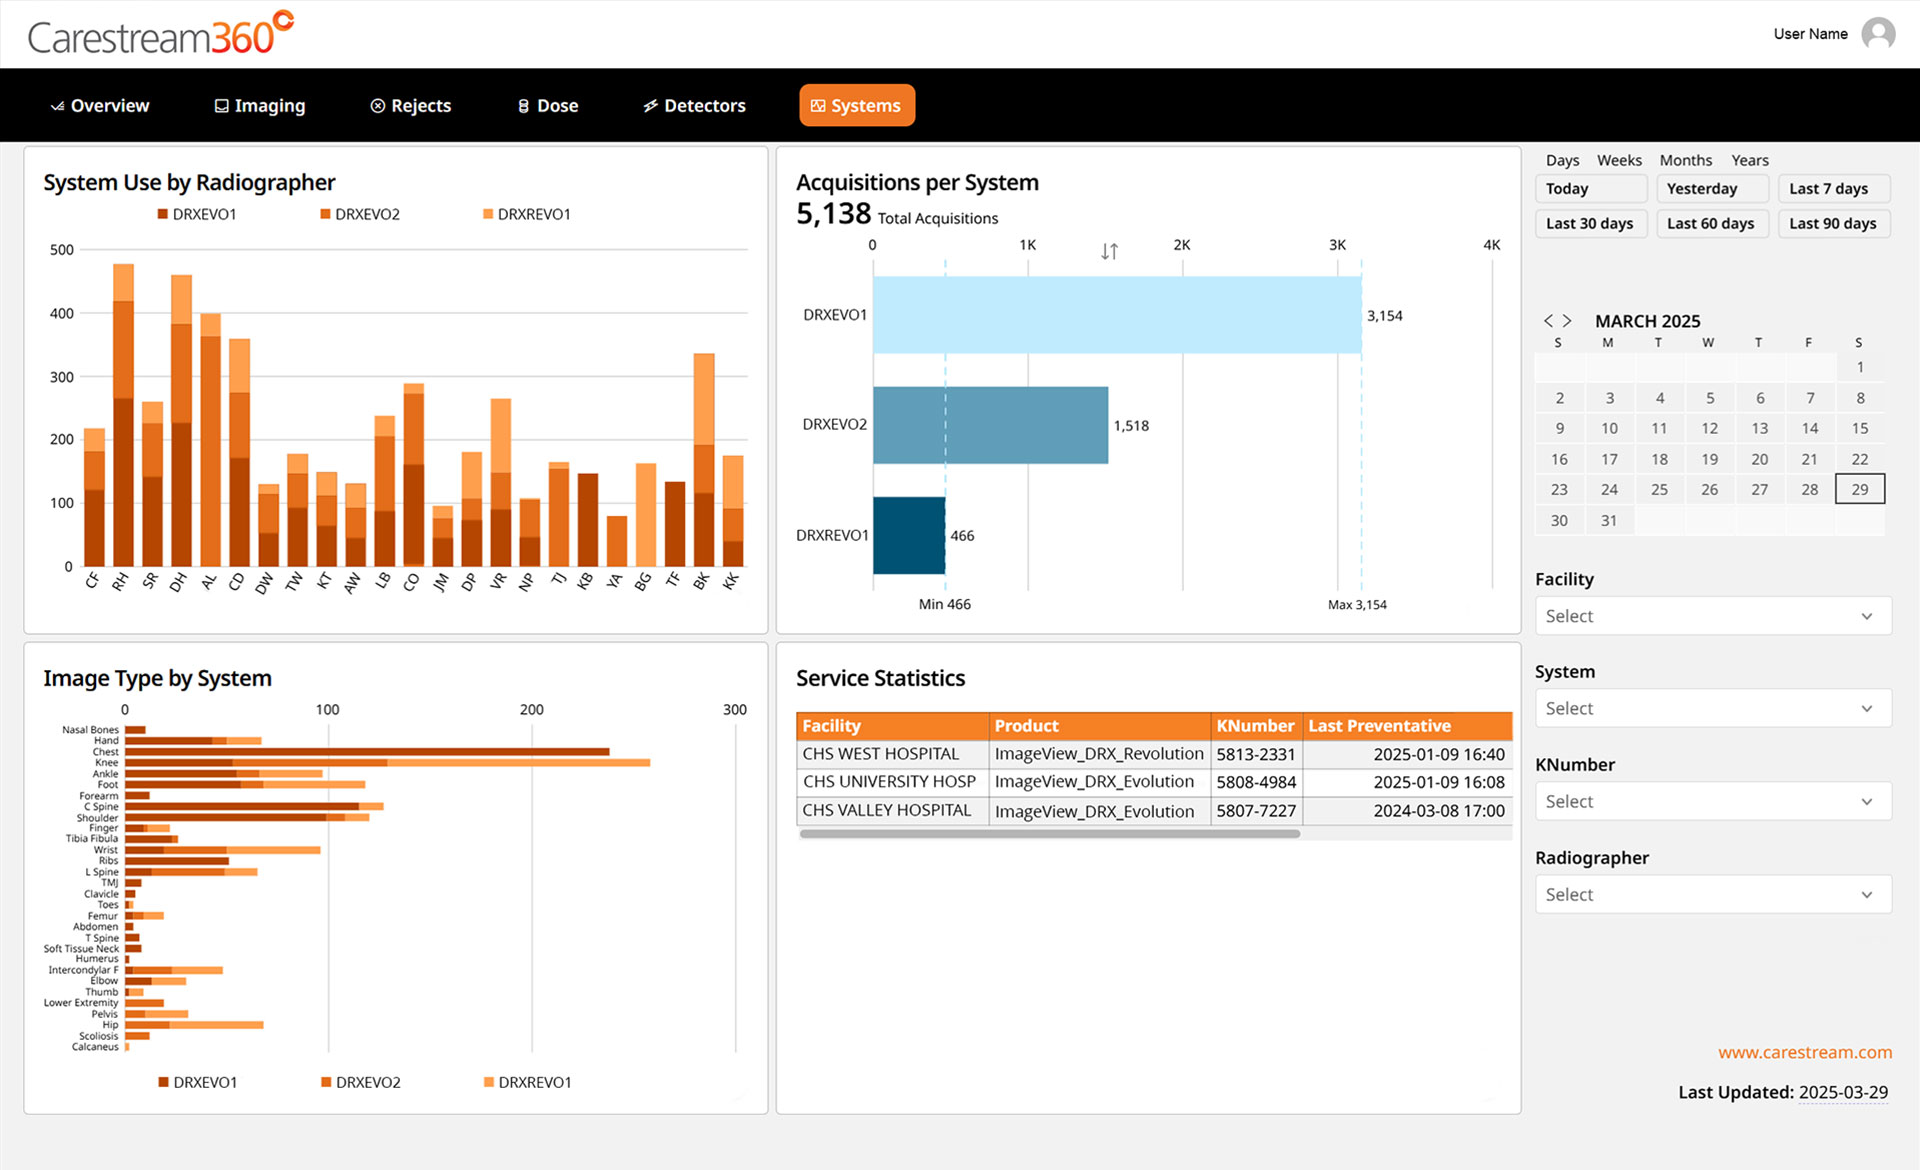

Carestream 360º is an advanced analytics dashboard designed to help radiology departments track key performance metrics, analyze imaging trends, and optimize operational efficiency. It automatically collects critical data from all connected Carestream DR systems and consolidates it into a single, intuitive dashboard, providing a comprehensive view to drive smarter decision-making.

Carestream 360º is designed with interactive tools that allow you to filter, explore, and export data effortlessly, empowering you to gain insights faster, interact intuitively, and make informed, data-driven decisions.

- Filter with Ease – Quickly refine data using intuitive, pre-set filters that allow you to focus on the metrics that matter most.

- Drill-Down Analysis – Dive deeper into trends and performance metrics to support more informed decision-making.

Key Insights to Optimize Performance

Carestream 360º transforms complex performance metrics into clear, actionable insights through a series of intuitive dashboard pages. Designed for efficiency, it helps you: